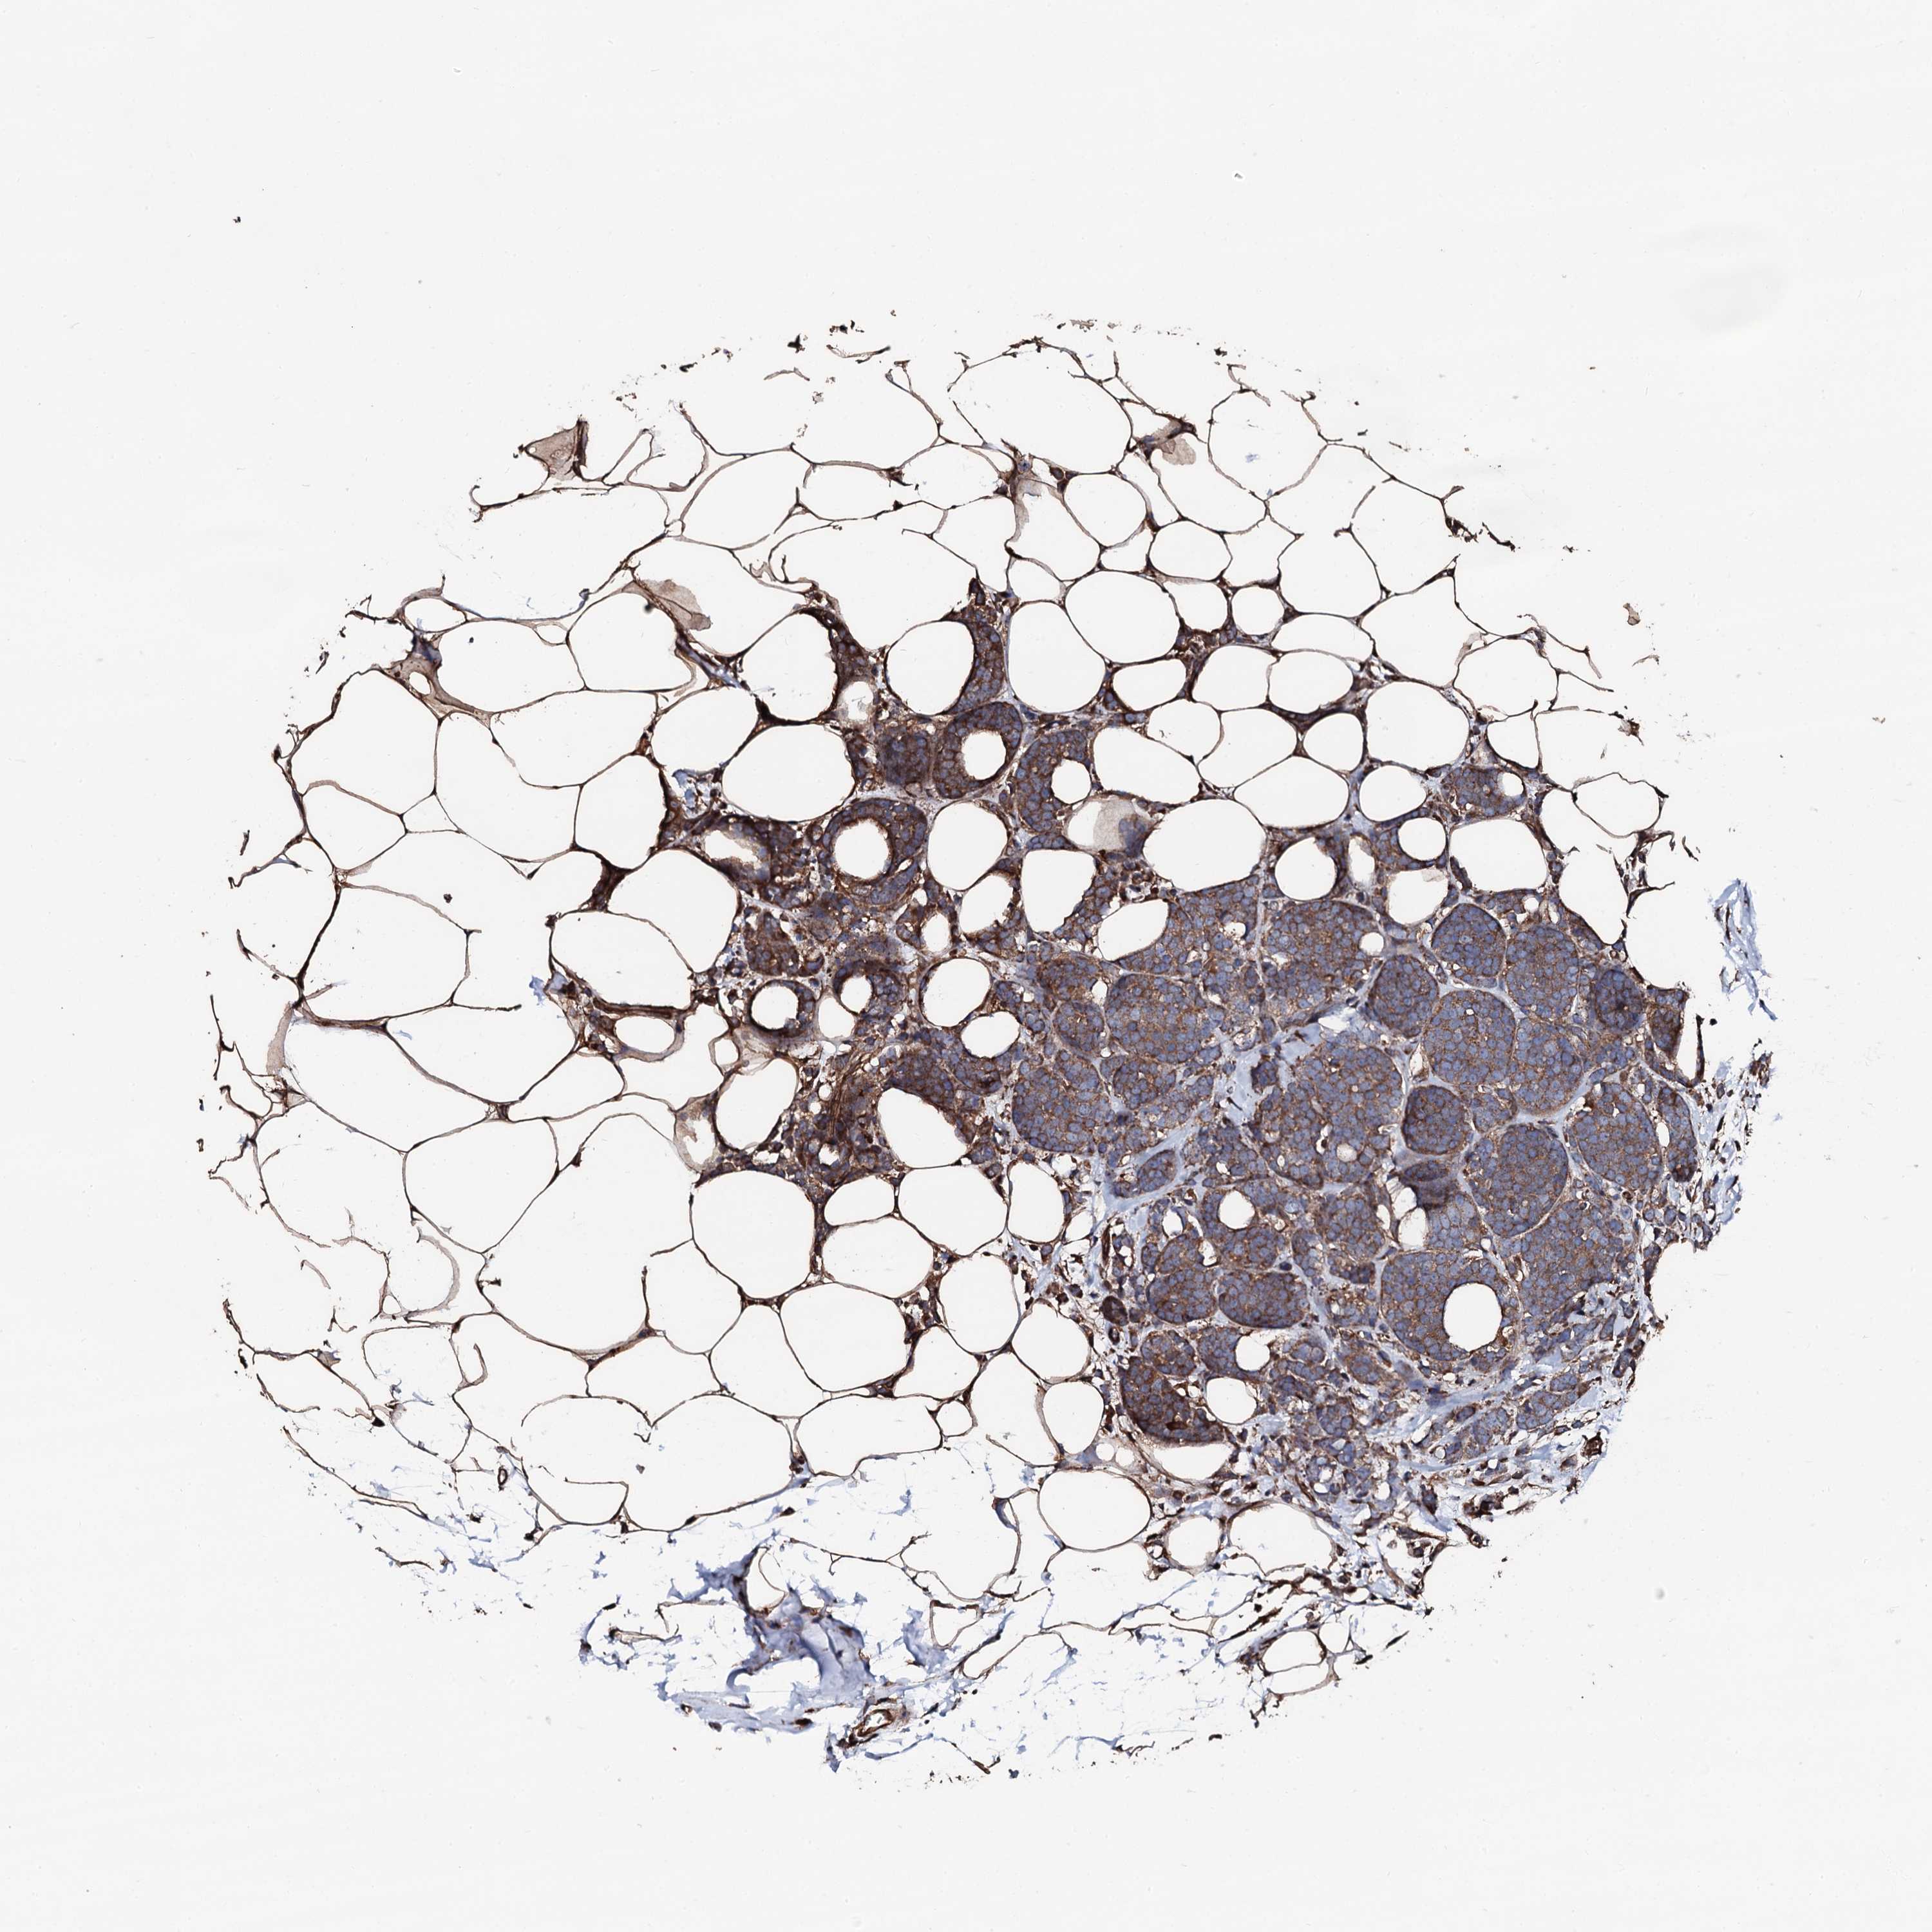

CANCER BREAST CANCER Show tissue menu

BRCA TCGA BRCA VALIDATION PROTEIN EXPRESSION